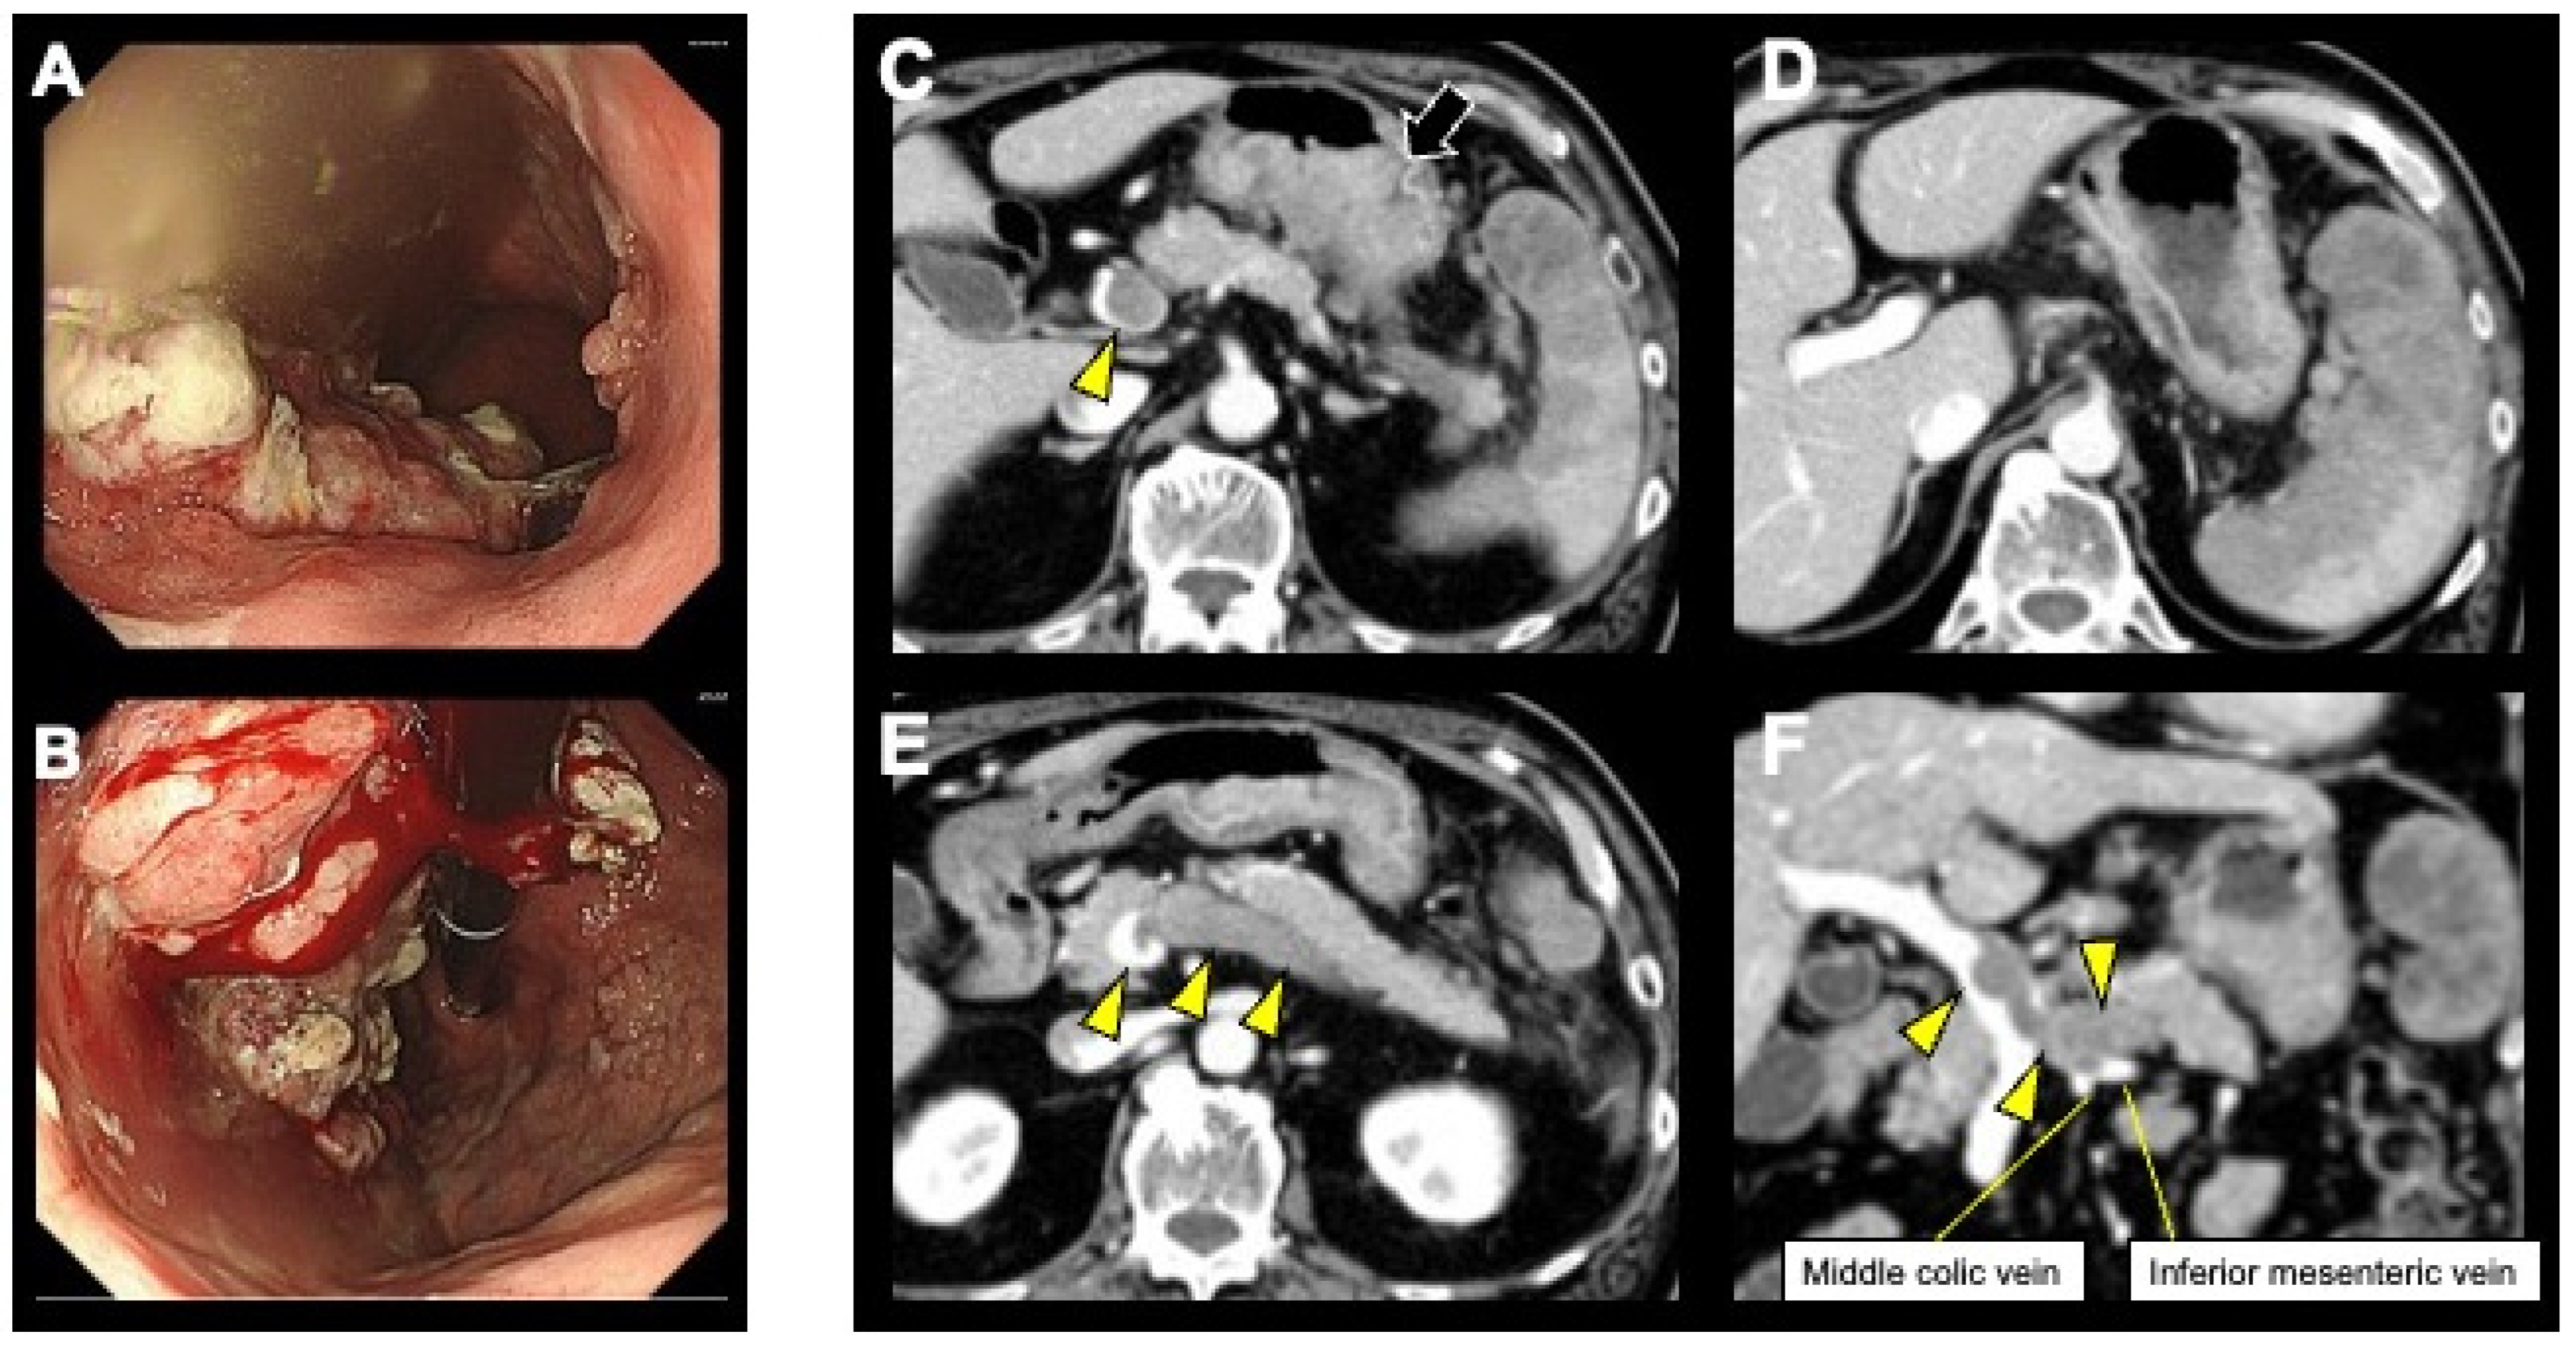

2. Case Presentation